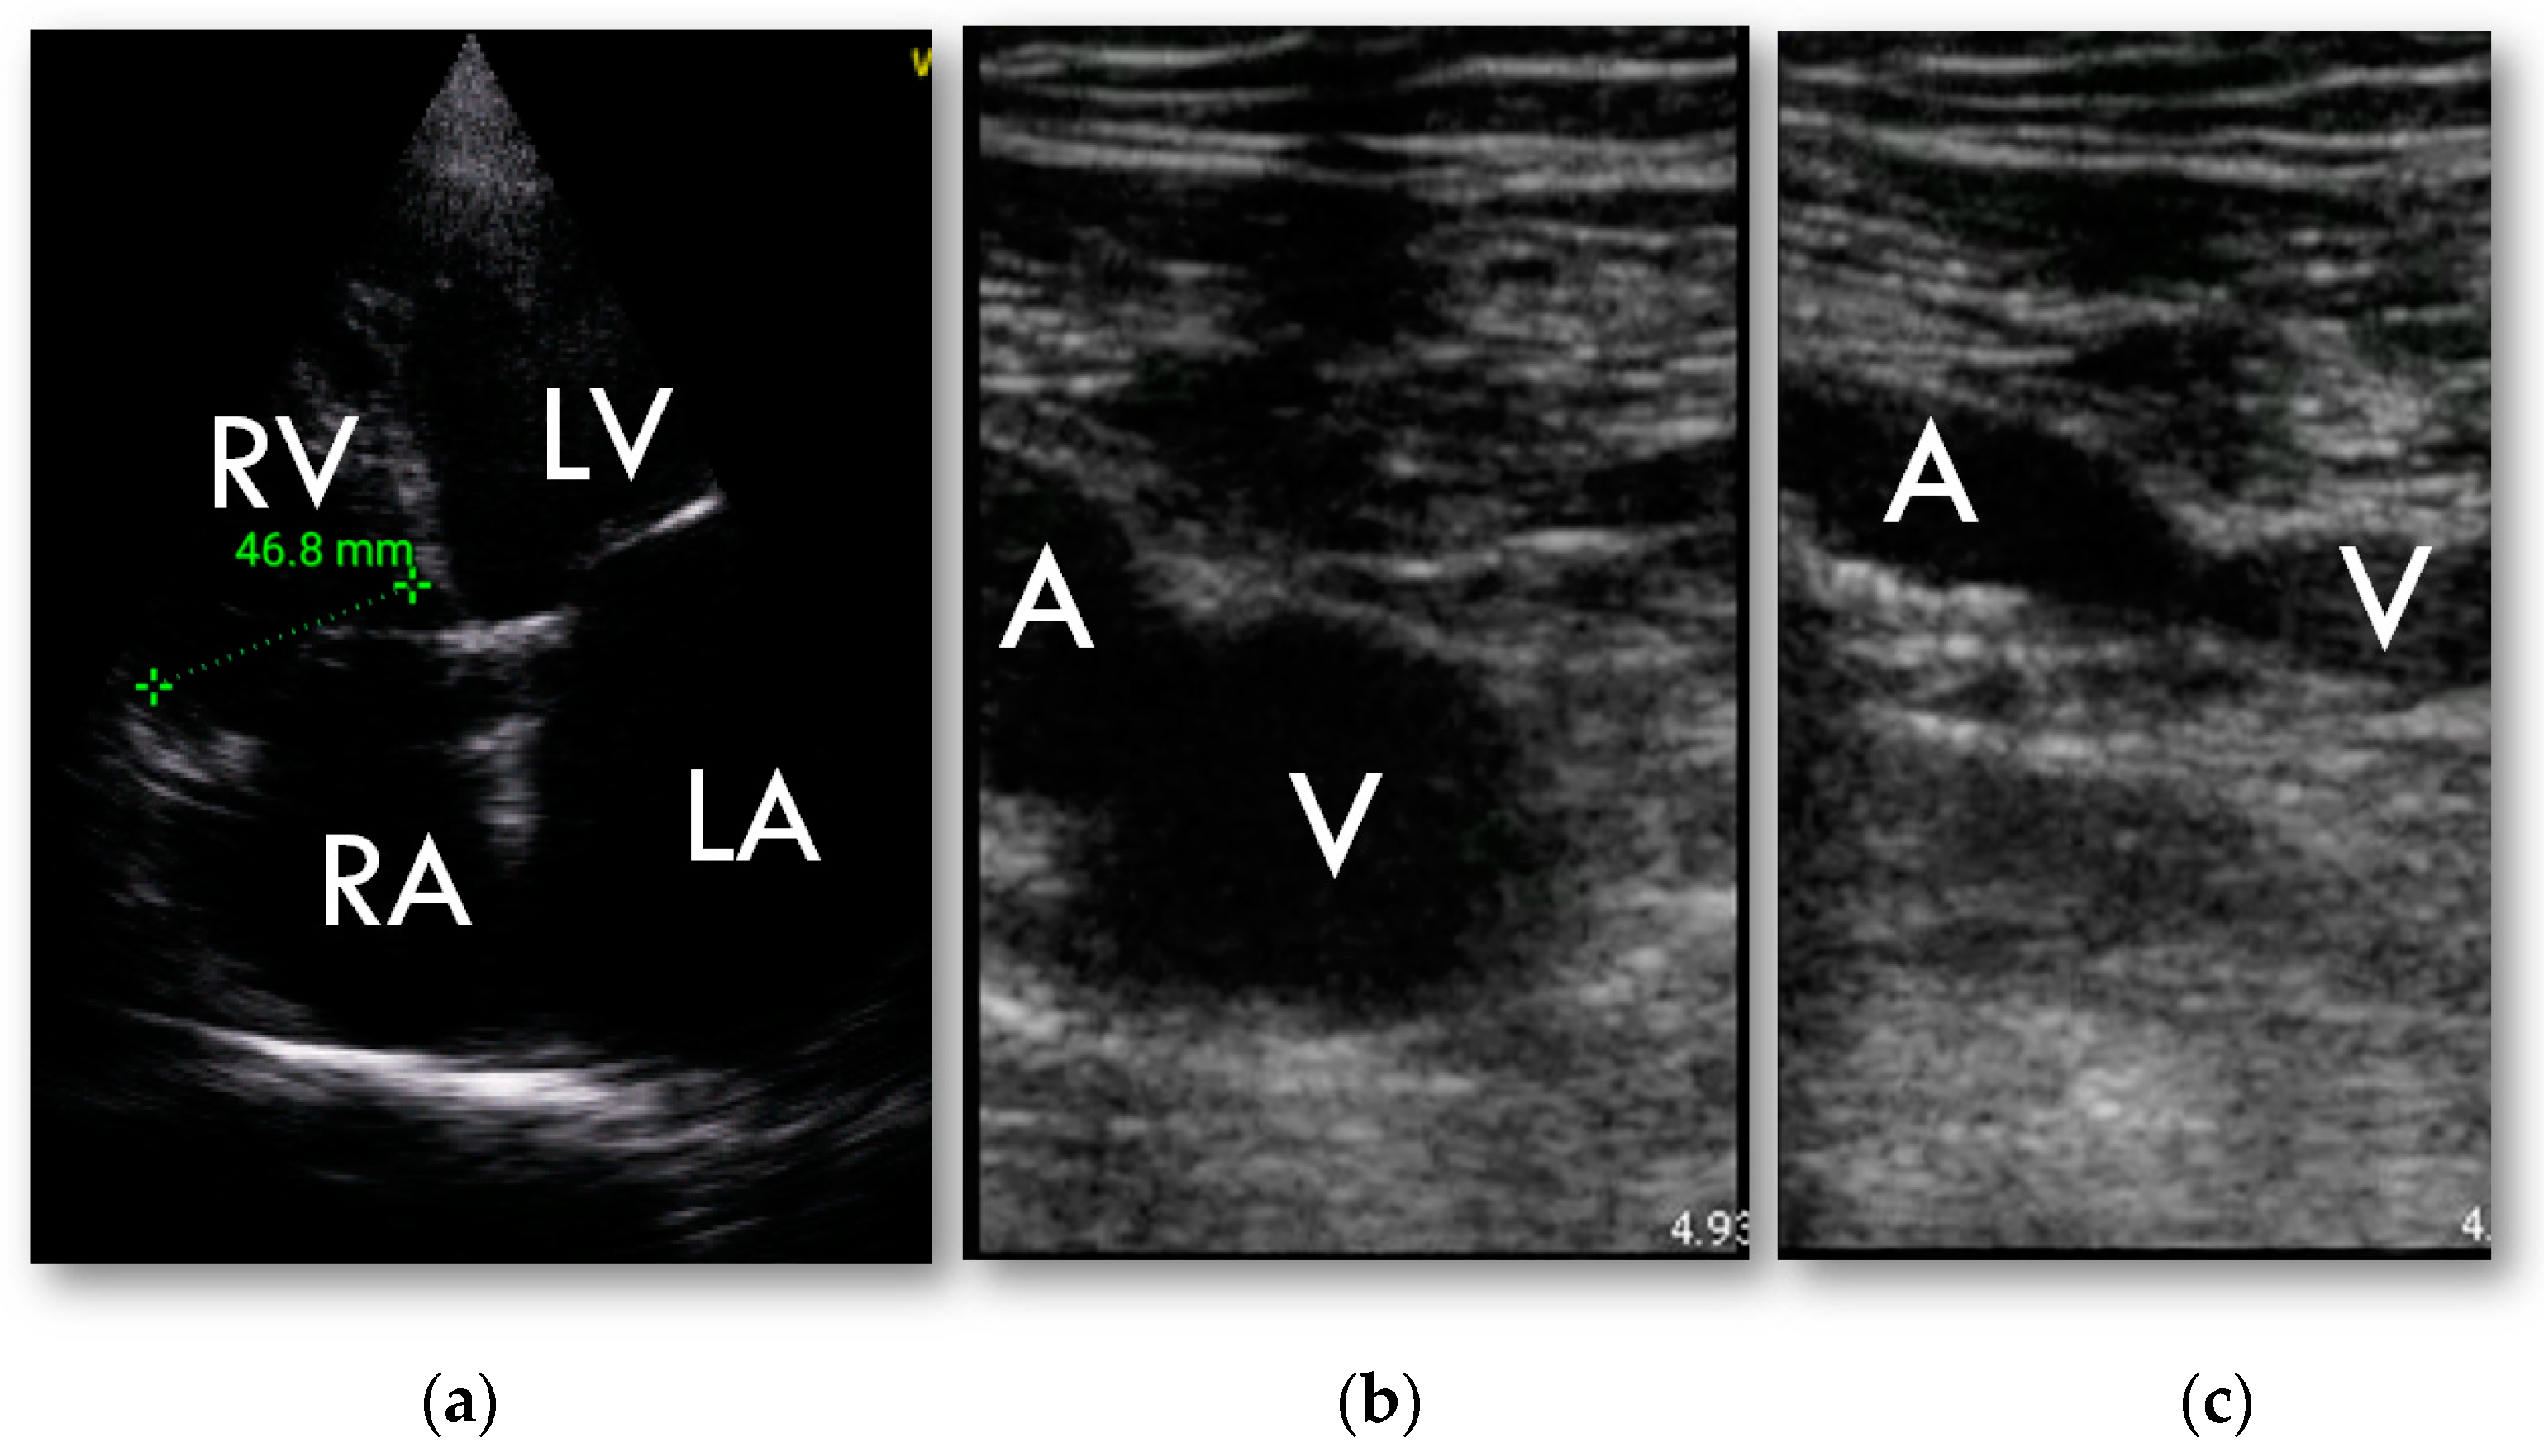

RV was found to be dilated in HUD examination in 27 patients (43%) and in 31 patients (49%) in full echocardiographic examination. Weighted kappa was 0.803 ± 0.074, 95% CI 0.665–0.953.

3.3. Vein Compression Ultrasound

The feasibility of compression ultrasound tests performed with the use of HUD was high. In total, 100% of femoral vein and 94% of popliteal veins imaging were classified to be sufficient for reliable assessment. In two patients the CUS result was positive, consistent with further observed clinical course.

3.4. Pulmonary Embolism Diagnosis

In 20 patients (32%), pulmonary embolism was confirmed by angioCT—in 10 among them embolism was limited to the subsegmental arteries. RV enlargement treated as a Graph was changed as suggested.marker of PE had low sensitivity and specificity (60% and 65%, respectively), AUC = 0.62 ± 0.067; 95% CI 0.495 to 0.744; p = 0.06. Positive predictive value of RV enlargement as a marker of pulmonary embolism was 45% and negative predictive value was 78%. For proximal PE, only the area under the ROC curve increased to 0.721 (±0.074; 95% CI 0.593 to 0.826; p = 0.003) sensitivity and specificity were 80% and 64%, respectively, PPV 30%, NPV 94%.

In both cases of positive CUS pulmonary embolism was confirmed in angioCT (Figure 4).

Figure 4.

HUD examination; (a)—RV focused 4-chamber apical view, basal dimension; (b,c)—compression ultrasound test of common femoral vein: (b)—without compression; (c)—abnormal examination in deep vein thrombosis. Vein is not entirely occluded.